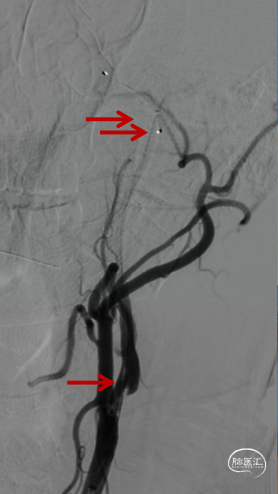

微导管越过大脑中动脉血栓后,以4-20mm Solitaire AB支架,配合6F 115cm SKATHI远端通路导管取栓一次,复查造影大脑中动脉血栓通畅,远端仍有少许血栓,观察后血流能够维持。

回撤SKATHI远端通路导管至C3段,通过导管再次释放SPIDER保护伞,回撤导管至颈总动脉,造影见C1段严重狭窄,以4-30mm球囊扩张狭窄段,复查造影狭窄段好转,远端再次闭塞,考虑斑块或血栓脱落,立即置入7-40 wallstent支架。

复查造影远端仍然闭塞,负压状态上行SKATHI远端通路导管回收保护伞并抽吸血栓,可见保护伞及大量血栓取出,复查造影C3段仍有血栓。再次上行SKATHI远端通路导管抽吸取栓,复查造影示远端血流通畅。